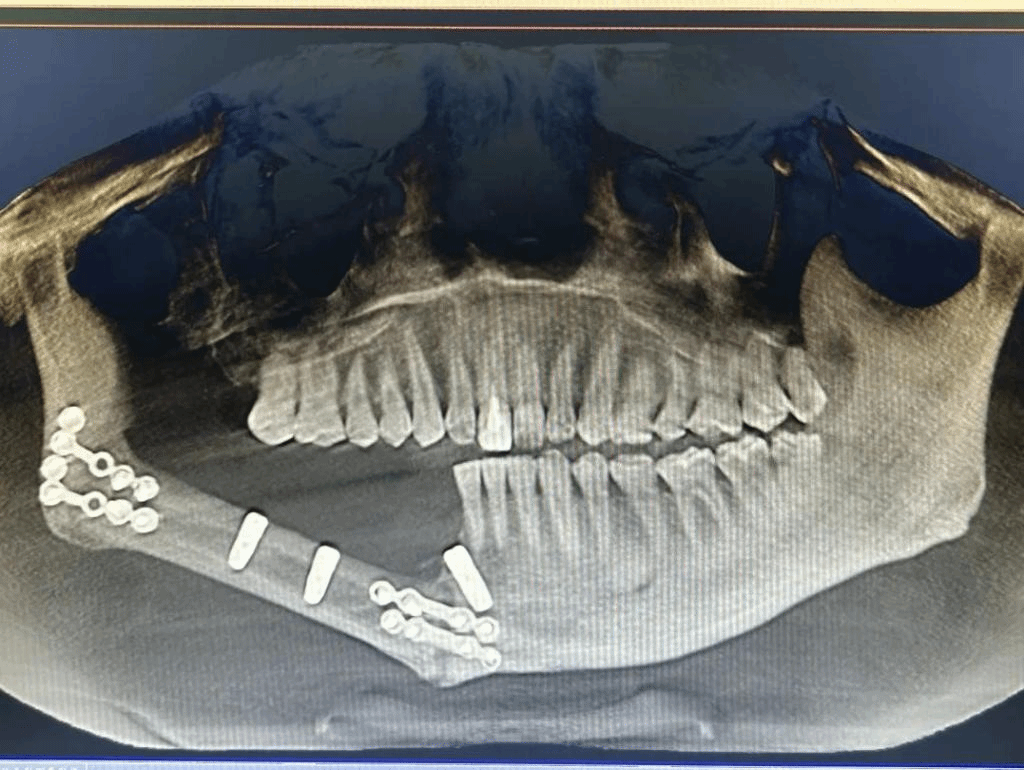

为进一步恢复患者的咀嚼功能,口腔颌面肿瘤外科副主任凌彬联合口腔修复种植科副主任姬晓炜,结合患者病情制定治疗方案。由于移植后下颌骨形态不规则,且腓骨较细、骨量不足,腓骨瓣上方还存在软组织覆盖,右侧下颌骨切除后损失牙齿较多,治疗团队判断需要植入种植牙来恢复患者咀嚼功能,决定为患者实施5G数字化动态导航下颌骨缺损腓骨重建后种植体植入手术。

经导航拟定种植方案(左)种植术后影像(右)

相比于传统定位技术,5G数字化动态导航能够更精准的判断最佳种植位置和方向,缩短手术时间,降低安全风险。经过对患者口腔颌面锥形束CT影像的测量,团队确定了手术方案,在5G数字化动态导航下在患者右侧下颌腓骨体突破双皮质层,精确植入3枚种植体,全部初始扭力合格稳固。不到一小时即完成手术,植入位置与导航设计完全一致,术后患者无明显出血、肿胀、疼痛等不良反应,复查种植体在位,无脱落迹象。